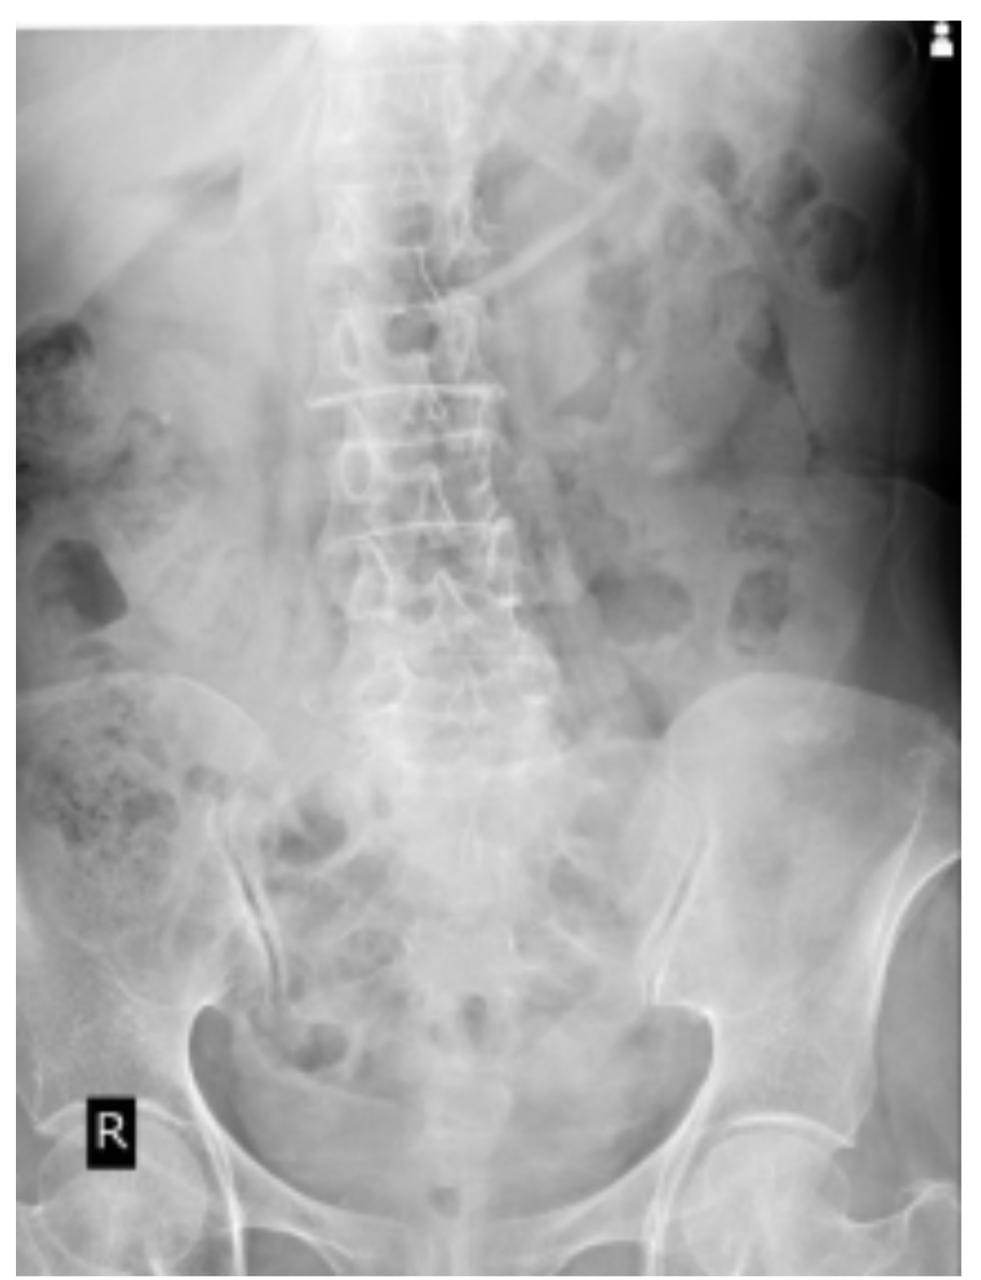

USG ABDOMEN:

CHEST X-RAY PA VIEW:

MRI:

Patient underwent ECSL for Right Renal stones (ECSL) 6 years back, Hysterectomy 20 yrs back and Left Cataract Surgery 6 yrs back.